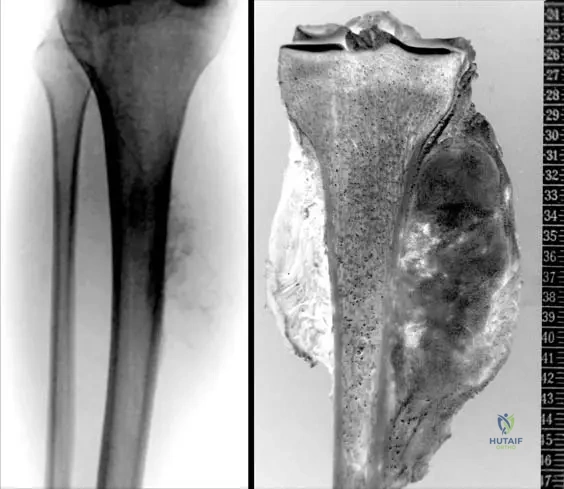

A 16-year-old male presents with pain and swelling in his mid-tibial diaphysis. Radiographs show a partially mineralized mass on the surface of the bone with ill-defined margins. The mass appears denser near the cortex, with an unmineralized soft tissue component superficially. There is no apparent involvement of the underlying medullary canal in the early stages.

Rationale: Periosteal osteosarcomas are grade 2 surface tumors usually affecting the diaphysis of long bones. They present with a partially mineralized mass on the surface of the bone with ill-defined margins, denser near the cortex, and an unmineralized soft tissue component on the surface. Crucially, there is no involvement of underlying marrow in the early stage. This description matches the vignette and the provided image (Fig. 8.70 a, b) of a periosteal osteosarcoma of the tibial diaphysis. Parosteal osteosarcoma is heavily mineralized and metaphyseal. Conventional osteosarcoma is intramedullary. High-grade surface osteosarcoma is also surface but often more circumferential and heavily mineralized, with significant cortical reaction. Ewing sarcoma is typically lytic with an onion-skin periosteal reaction and small round blue cells on histology.